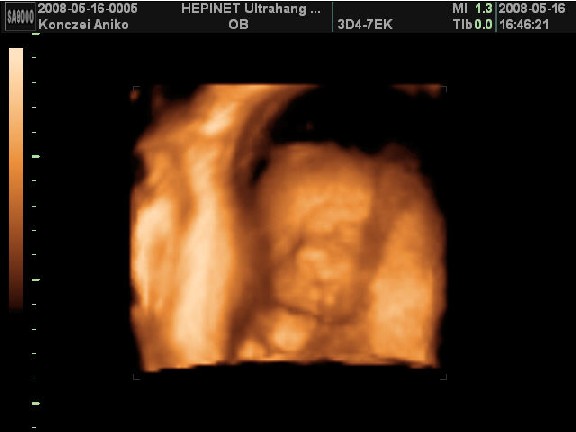

Voltam már uh-n 3x. Az elsőn 6 hetesen, mert barnáztam akkor 2 napig, majd 2 hét múlva is egy napig...A következő 10hetesen volt, mert már nem bírtam magammal, tudni akartam, h minden ok odabent. És végül a 12 hetes uh 12+3-on..ekkor minősítették 16+6-ra. A nemét még nem tudjuk, de nagyon kiscsajt szeretnék...hát majd kiderül. Most hétvégén majdnem elrohantam 4D-re, mert ismét nem bírok magammal...de szerencsére fullon voltak, meg a nő amúgyis le akart beszélni a 4D-ről, mondván csak 24hét után érdemes...szép. Így mostmár úgy döntöttem, hogy inkább kivárom a 3 hetet, amikoris hazalátogatok 5 napra. Jún. 5-én fogok elmenni 4D-re otthon, ahol kb 1/4-be kerül. Ja és nem fogjátok elhinni, de itt azért is külön fizetni kell, hogy a nemét megmondják.